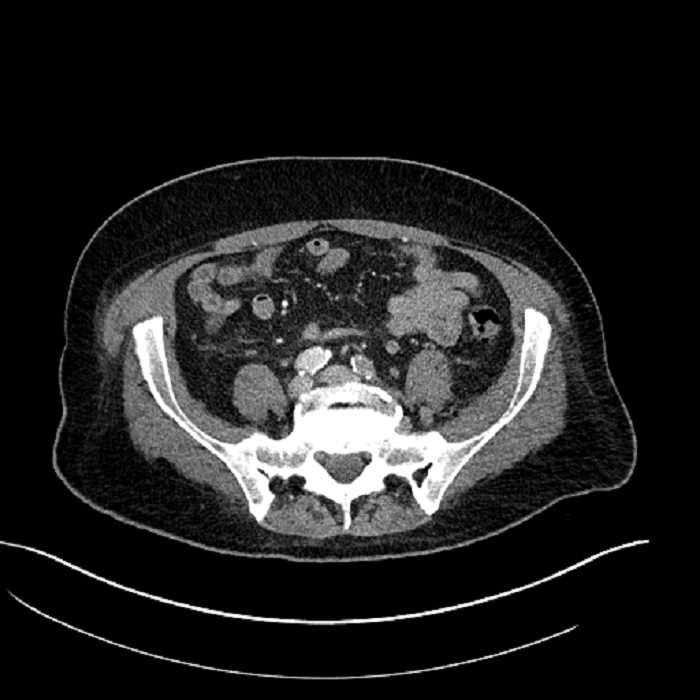

• High grade stenosis of the left common iliac artery, with the left internal and external iliac arteries remaining patent

High grade stenosis of the left common iliac artery. The left external and internal iliac arteries are patent.